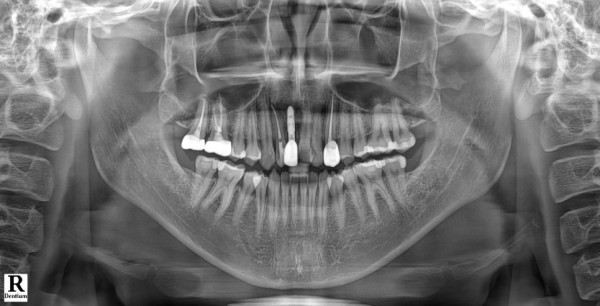

구강 검진 결과, 예상보다 상황이 심각했습니다.

오랜 기간 방치로 인해 전체적으로 충치가 상당히 진행된 상태였습니다.

상악 좌측 제1대구치(#16)에는 기존에 인레이 치료를 받으셨던

부위 아래쪽으로 2차 우식이 진행되어 인레이가 탈락된 상황이었고,

앞니 부분에도 상당한 우식이 관찰되었습니다.

전반적으로 여러 치아에 걸쳐 치료가 필요한 상태였죠.